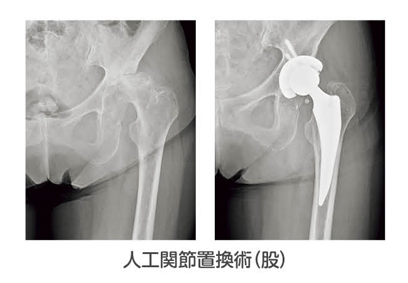

人工関節置換術

膝や股、肘、肩関節などに行われ、素材や手技の改良とともに、耐用年数も大きく伸びており、医療技術の進歩により、高齢の患者さまでも積極的にこの手術が行われるようになりました。